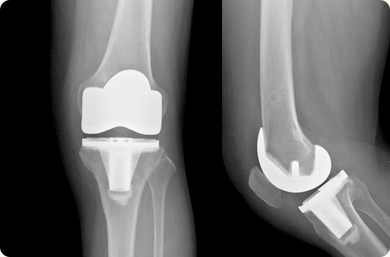

Àΰø°üÀý ¿¢½º·¹ÀÌ »çÁø

¹«¸­ °üÀý¿¡ ¹ß»ýÇÑ °üÀý¿°À¸·Î ÀÎÇÏ¿© °üÀý ¿¬°ñÀÇ ¾ø¾îÁü¿¡ µû¶ó ½ÉÇÑ ÅëÁõÀÌ ³ªÅ¸³¯ ¶§, ¼ö¼ú Ä¡·á¹ýÀ¸·Î ´â¾ÆÁø ¿¬°ñ¸éÀ» Á¦°ÅÇÑ µÚ Àΰø °üÀý·Î ´ëüÇÏ´Â ¹æ¹ýÀÔ´Ï´Ù.